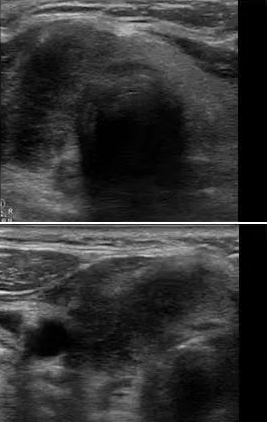

借助超声设备监测排卵是观察卵泡发育和确定排卵期的最准确方法,目前采用黑白超、彩超均可以达到监测卵泡效果。今天给大家介绍监测排卵中的细节问题。1.什么时候做?女性在做监测排···...